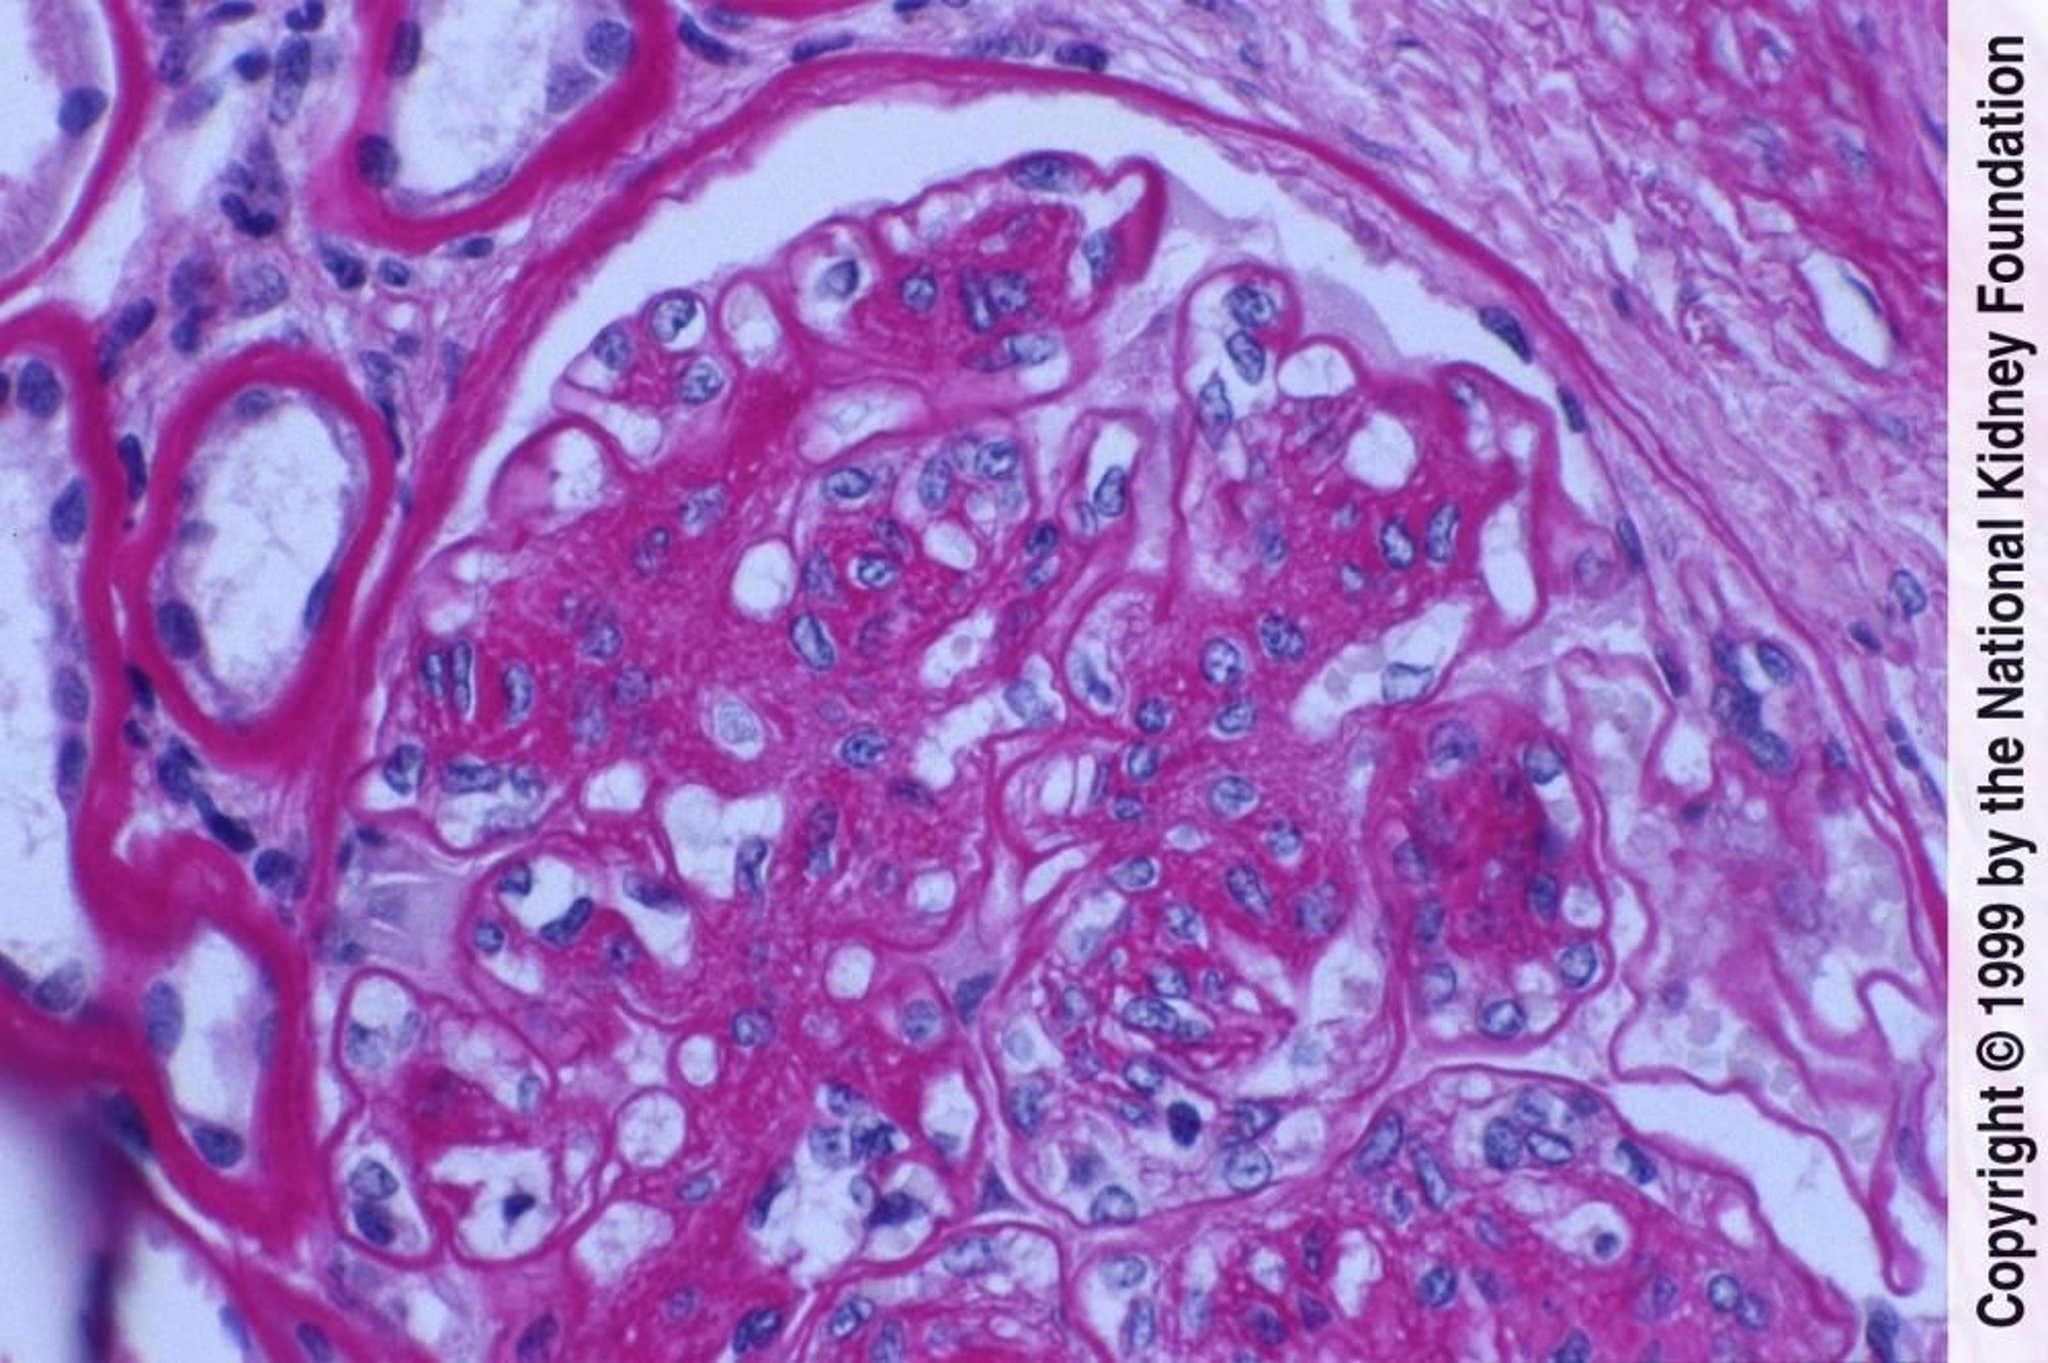

Néphropathie diabétique (prolifération des cellules mésangiales et expansion de la matrice)

La prolifération des cellules mésangiales et l'expansion de la matrice en cas de lésions endothéliales se manifestent ici par des membranes basales glomérulaires épaissies sans dépôts de complexes immuns évidents (coloration à l'acide périodique Schiff, ×400).

Image fournie par Agnes Fogo, MD, and the American Journal of Kidney Diseases' Atlas of Renal Pathology (voir www.ajkd.org).